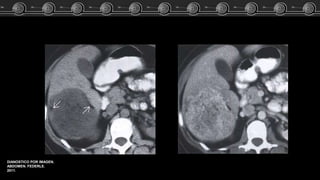

Adenoma, Hemangioma óHNF?? Caso Clínico Fem de 83 años…. El estudio TC demostró lesión focal a nivel del lóbulo izquierdo del higado. ARCHIVO DOCENTE DE TOMOGRAFÍA Y RESONANCIA C.M.C.